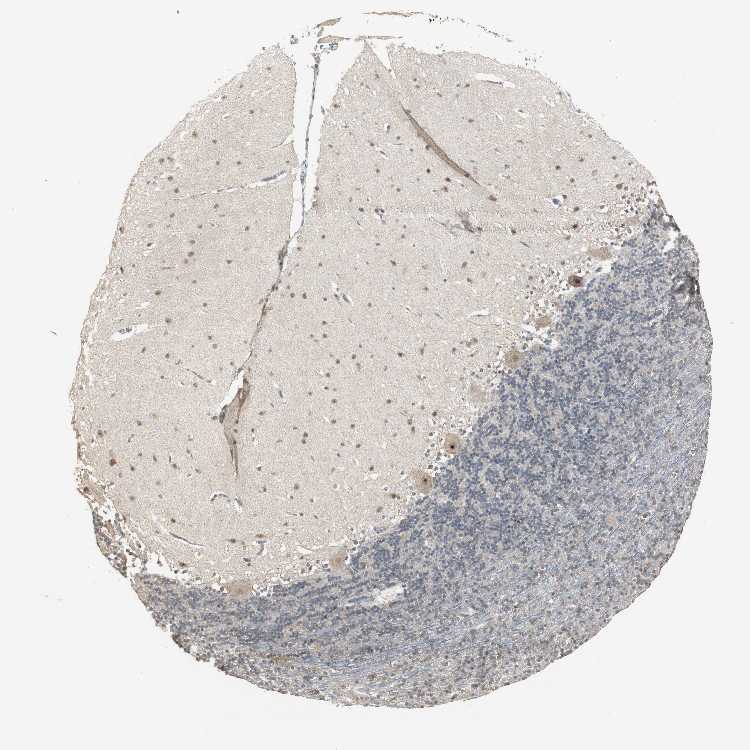

CEREBELLUM - Antibody stainingi

Antibody staining in the annotated cell types in the current human tissue is reported as not detected, low, medium, or high, based on conventional immunohistochemistry profiling in selected tissues. This score is based on the combination of the staining intensity and fraction of stained cells.

Each image is clickable and will lead to virtual microscopy that enables deeper exploration of all samples and also displays staining intensity scores, fraction scores and subcellular localization as well as patient and tissue information for each sample.

Antibody HPA005910

Purkinje cells High

Cells in granular layer Low

Cells in molecular layer Medium